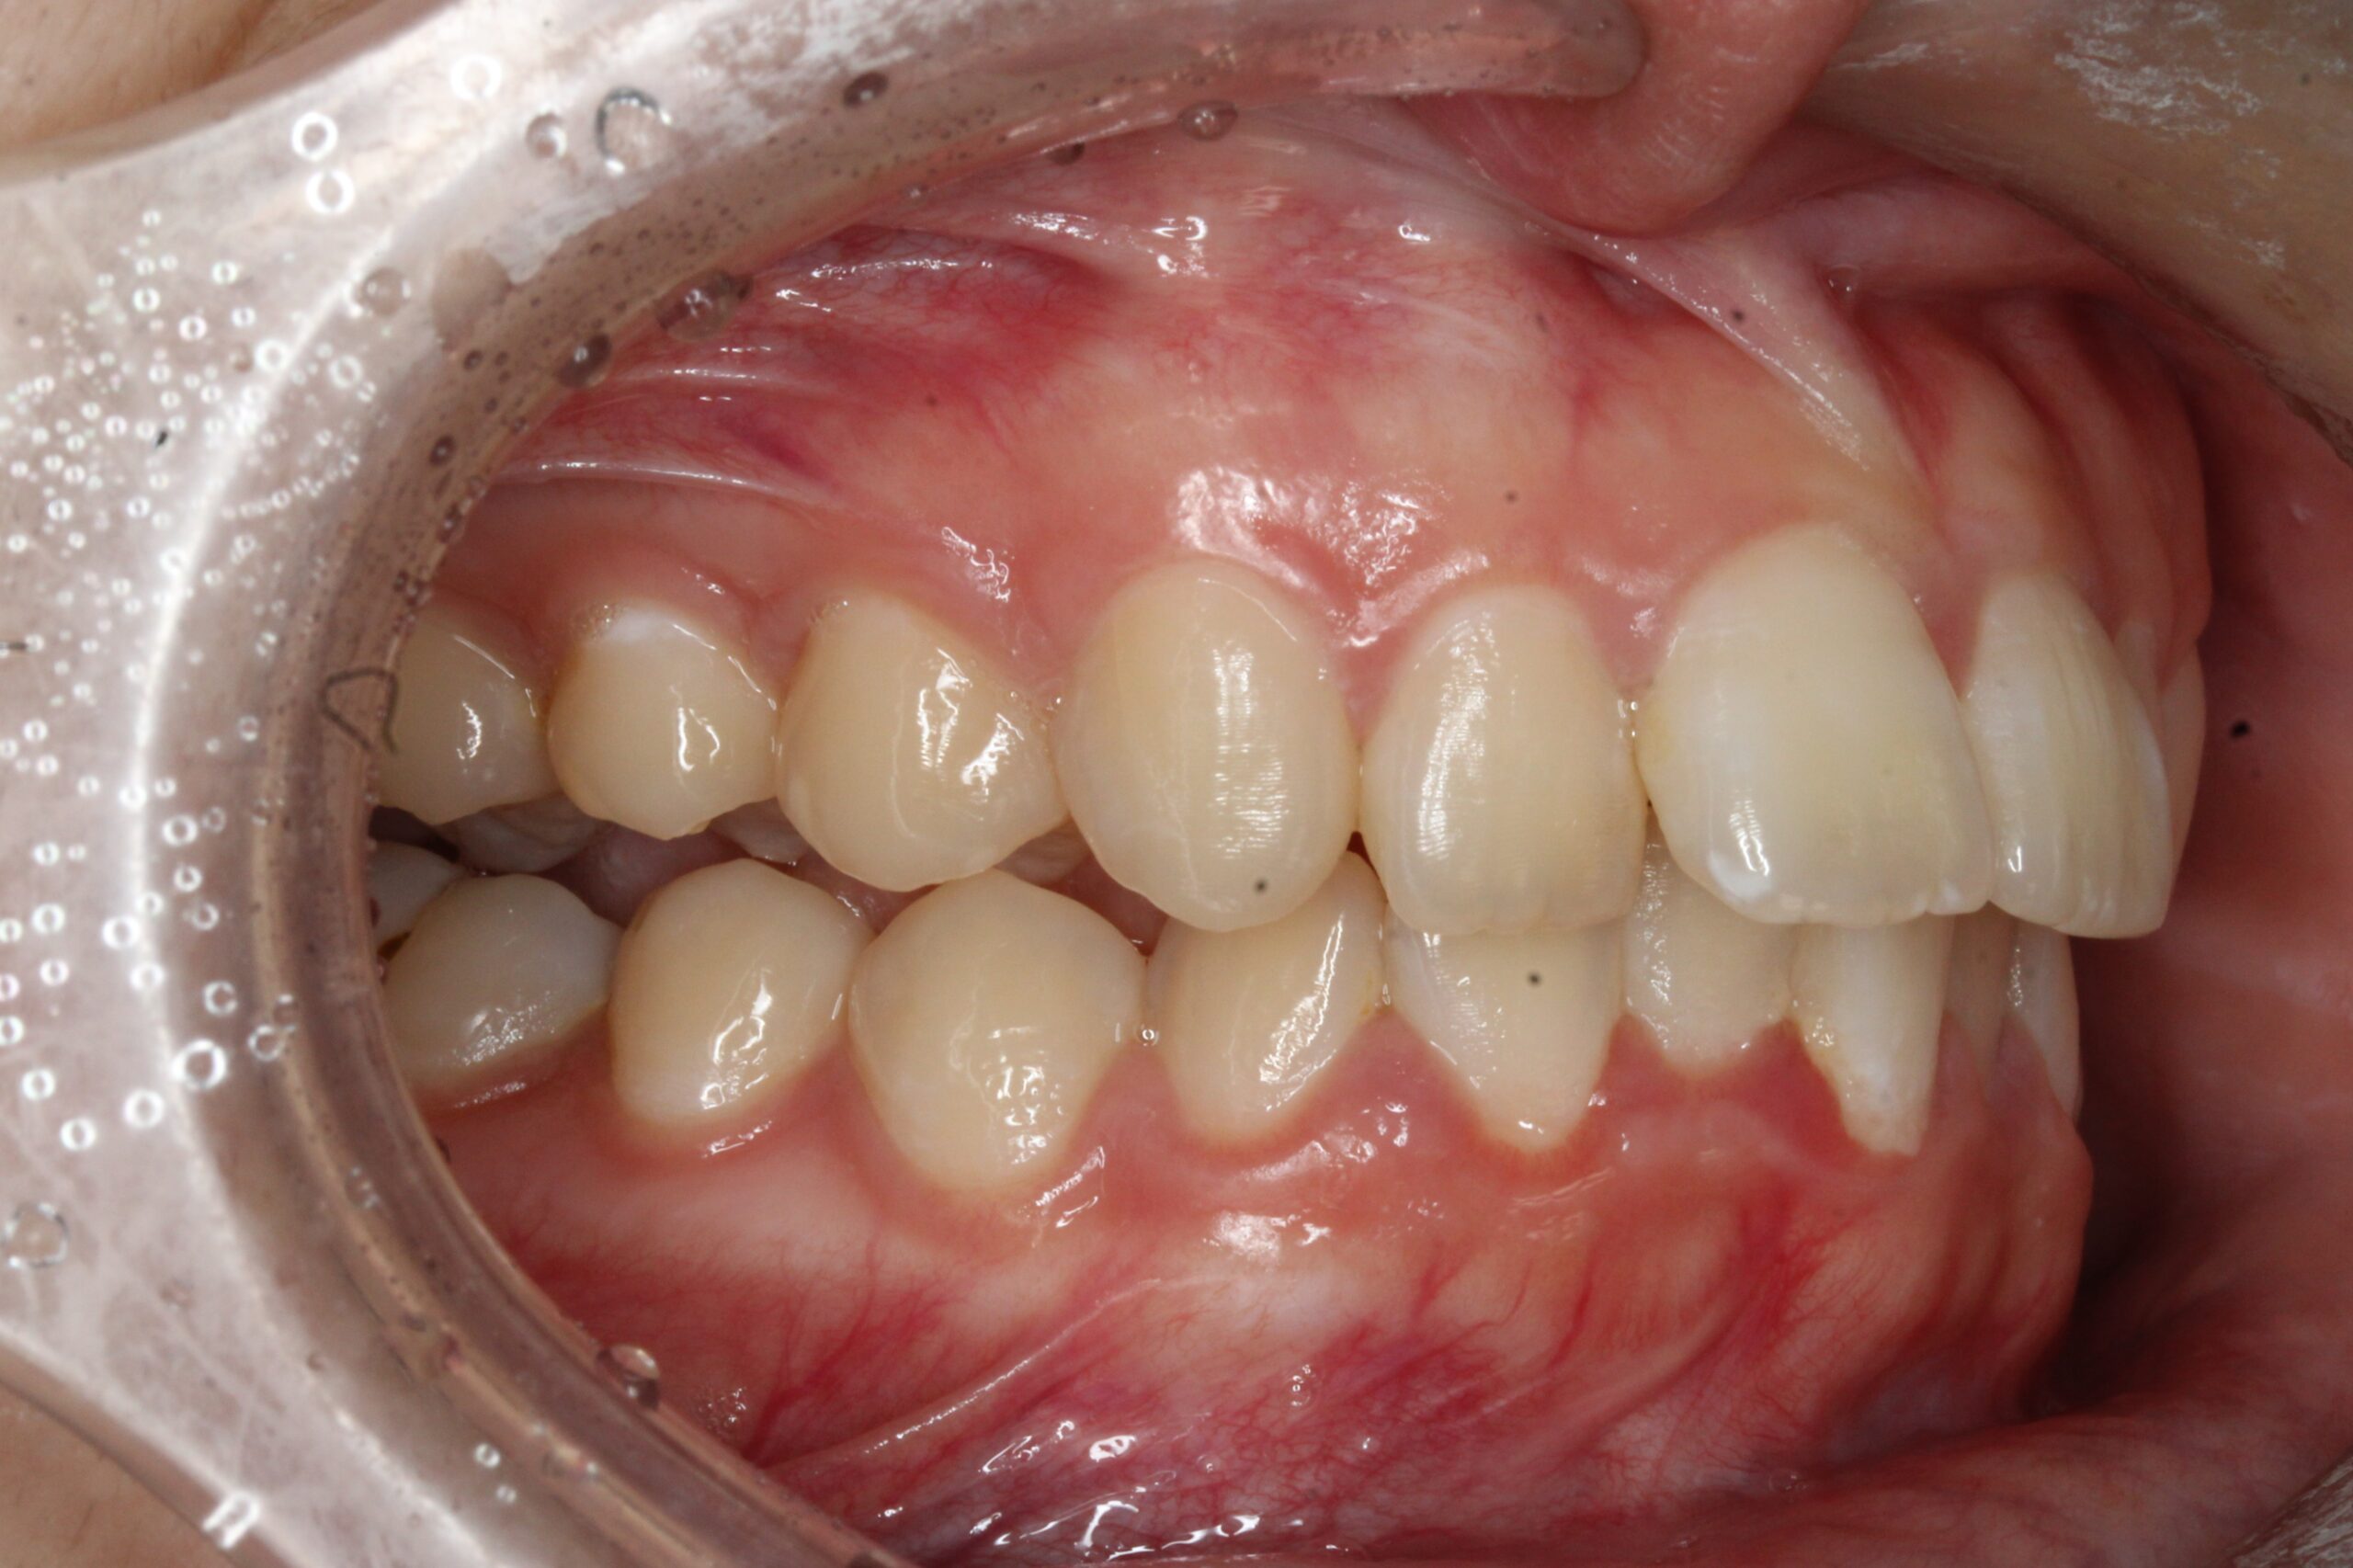

矯正術前:右側